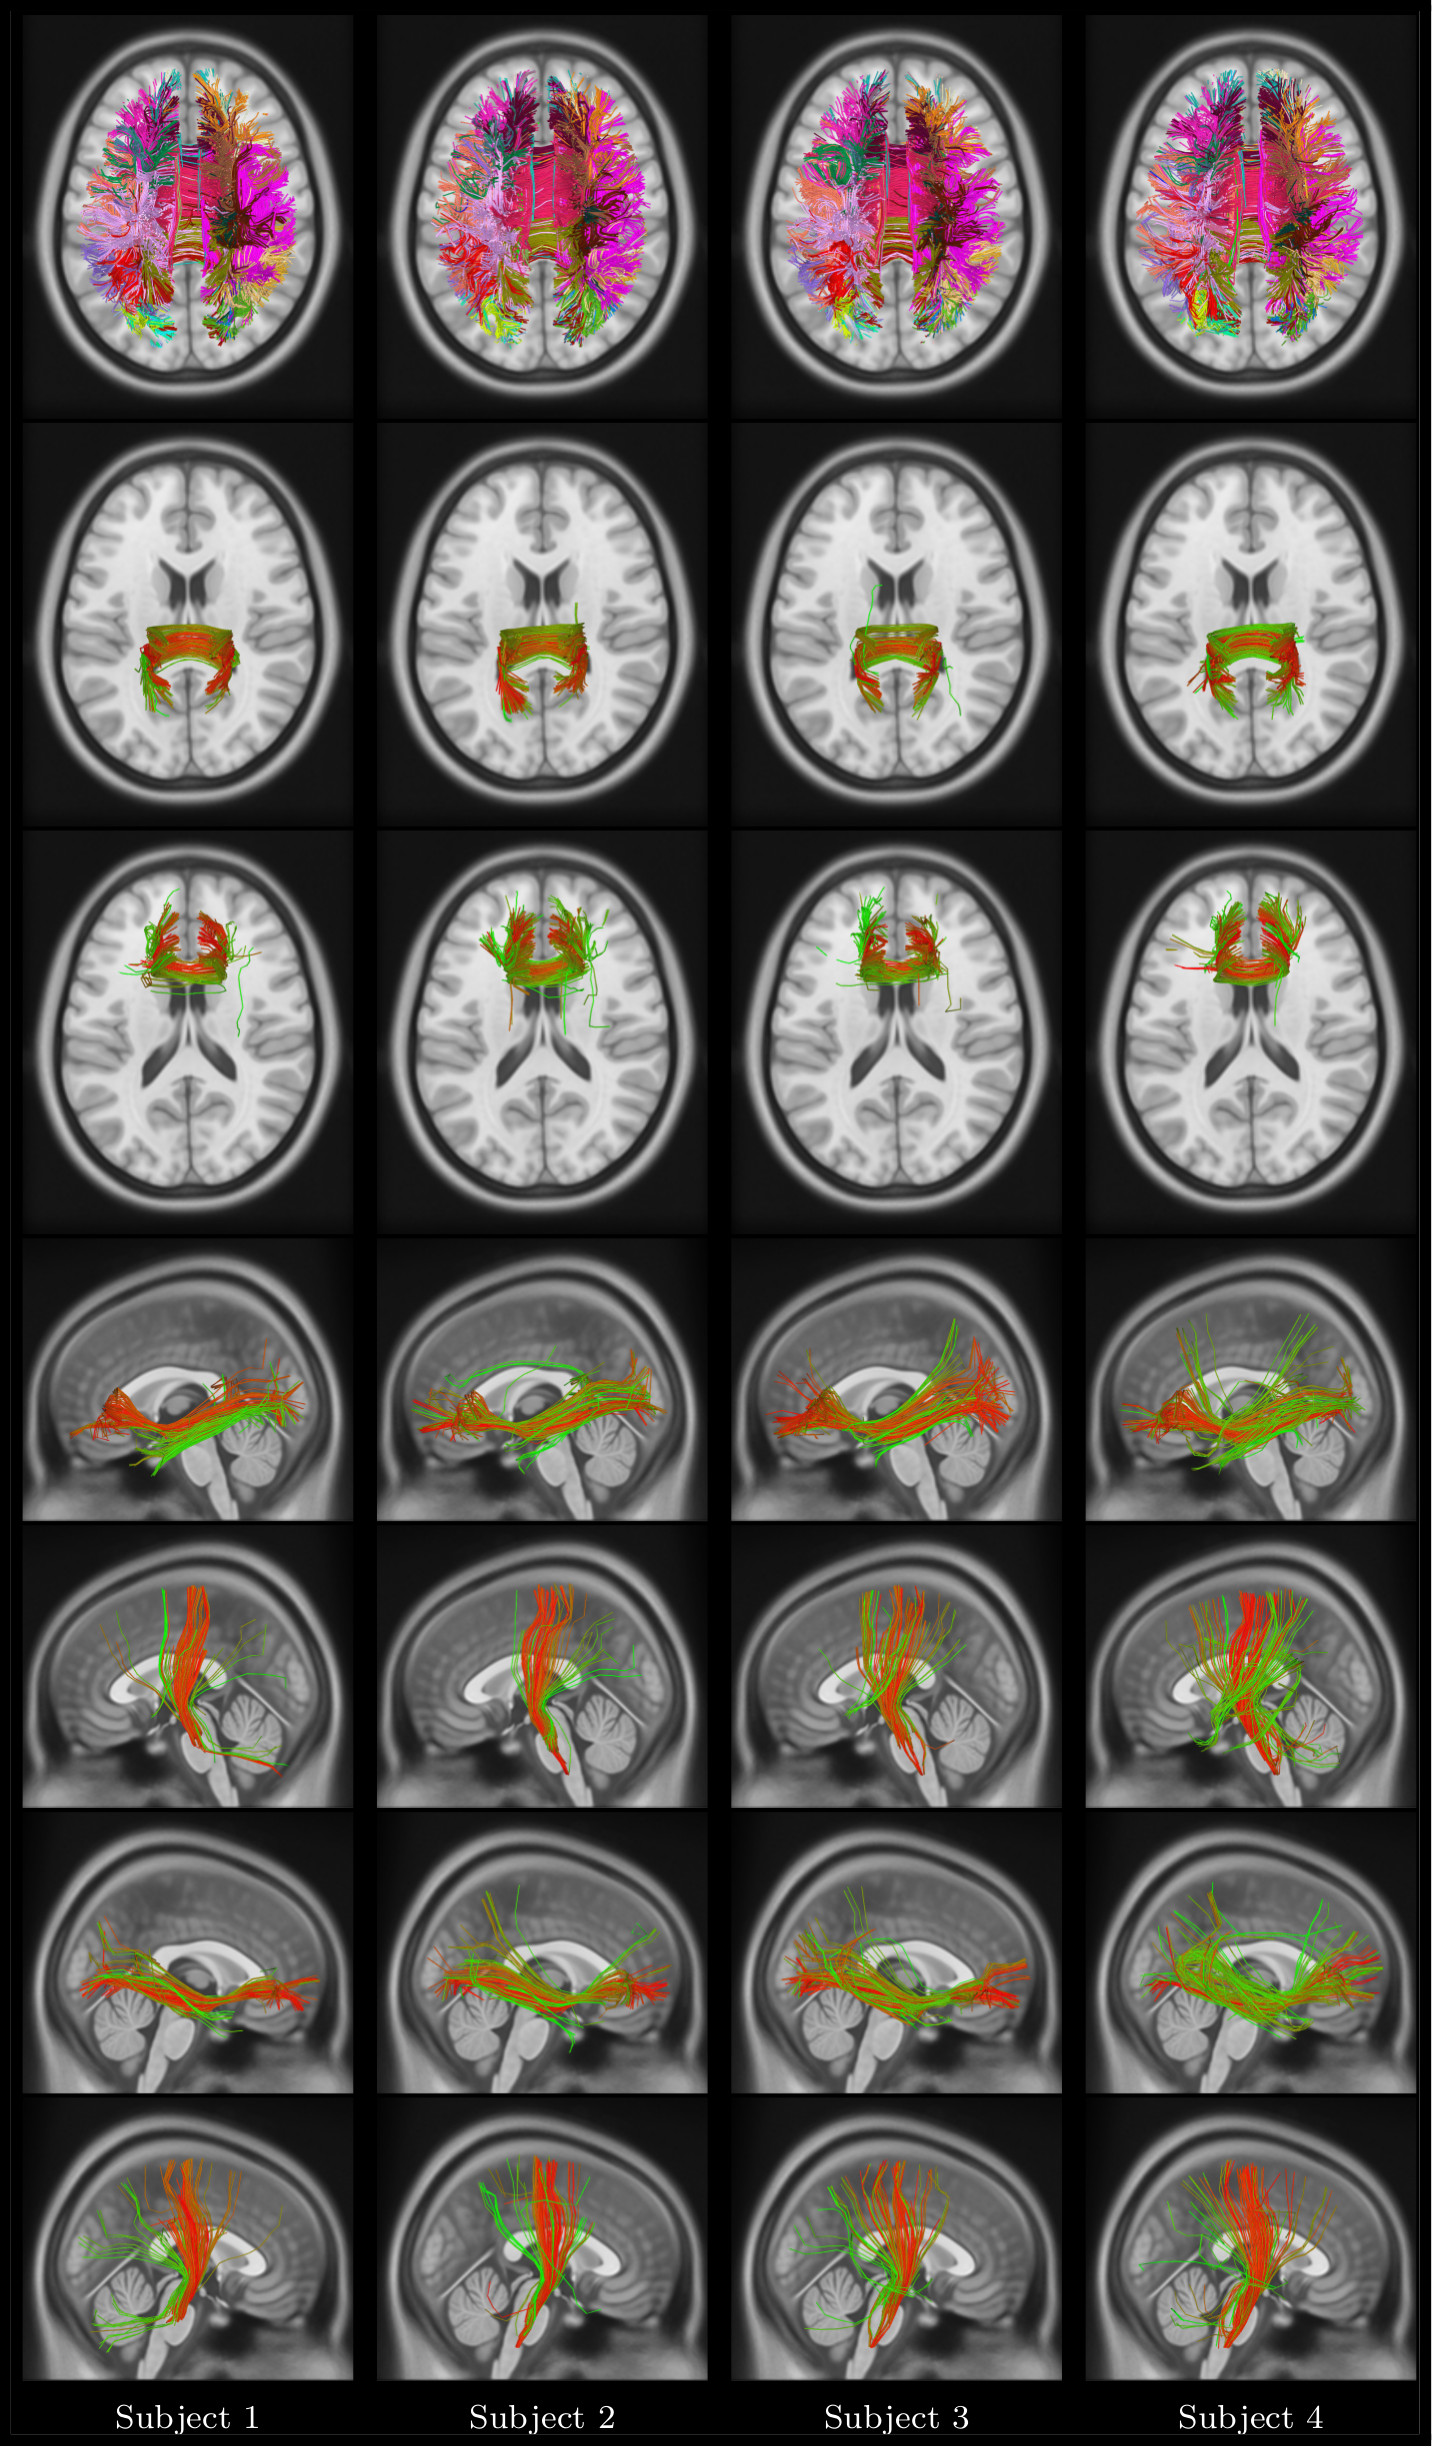

Refer to caption

Figure 9: Unsupervised multi-subject dictionary visualization. Four different dictionaries and corresponding bundles. Top row: Axial view of full dictionary with a unique color assigned to each bundle; Second row: Anterior Body, and Central Body bundles in Corpus Callosum; Third row: Left CST, and Left IOF bundles; Last row: Right CST, and Right IOF bundles. Each dictionary has a different color code, while the bundles respect that dictionary color-code. (m=50 bundles).

Figure 10: Automated segmentation visualization. Top row: full segmentation of 4 HCP subjects using dictionary D1, with a unique color assigned to each cluster, and same color code as D1. Rows 2-7: sparse code (bundle membership) visualization for the posterior body CC, anterior body CC, left IOF, left CST, right IOF, and right CST bundles. Membership values are represented by a color ranging from green (no membership) to red (highest membership).

The bundles encoded by these dictionaries are depicted in Figure 9. Moreover, segmentation results obtained for 4 different subjects using dictionary D1 are shown in Fig. 10. For each subject, we give the full segmentation as well as membership values for CC, left/right IOF, and left/right CST bundles. Additionally, to analyze the impact of sampling streamlines from a subject, segmentation results for 555 instances of subject 1 using D1 are provided in Supplement material. Once more, while we observe variability across segmented streamlines from different subjects, the results obtained by our method are globally consistent across subjects. Similar consistency is found across multiple instances of the subject 1 (see Supplement material, Fig. 5).